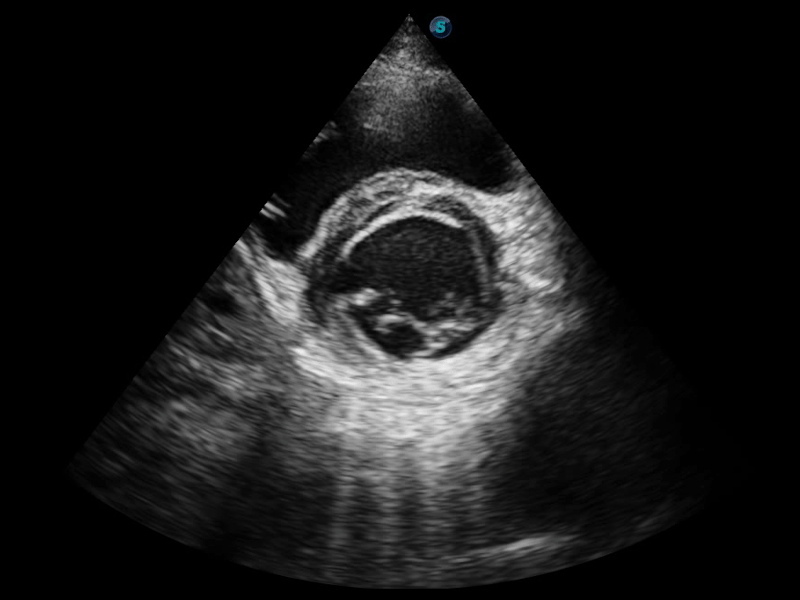

S-Fetus 产科扫查助手

S-Fetus基于大数据深度学习算法,能够帮助您在产前筛查过程中智能识别胎儿标准切面、自动测量并录入报告。一个按键,即可智能、精准、高效地获取胎儿生理指标,极大简化您的产科检查操作。